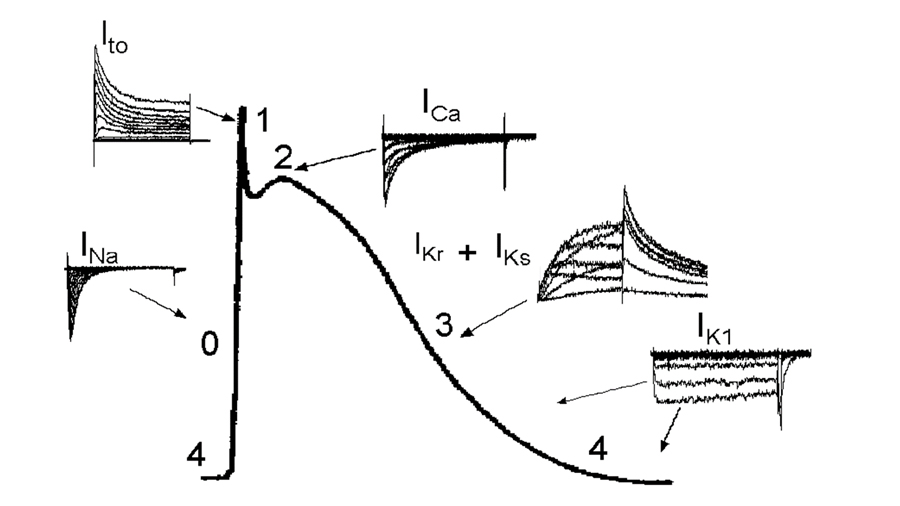

The NOVA team has been involved in ion channel research since the 1980’s. They have a long history of providing data for regulatory guidelines. For instance, we conducted the hERG screening for the original ILSI/HESI safety study which became the groundwork for the current S7B guidelines, and members of our team have been contracted by the FDA to provide ion channel screening in support of the new CiPA safety assessment guidelines. NOVA has worked with 100’s of companies along with multiple government agencies to help de-risk compounds.